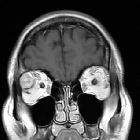

MRI

Signal characteristics include:

- T1: intermediate intensity lacrimal fossa mass

- T2: usually hyperintense

- T1 C+: heterogeneous enhancement

- DWI and ADC: diffusion restriction of the peripherally enhancing component